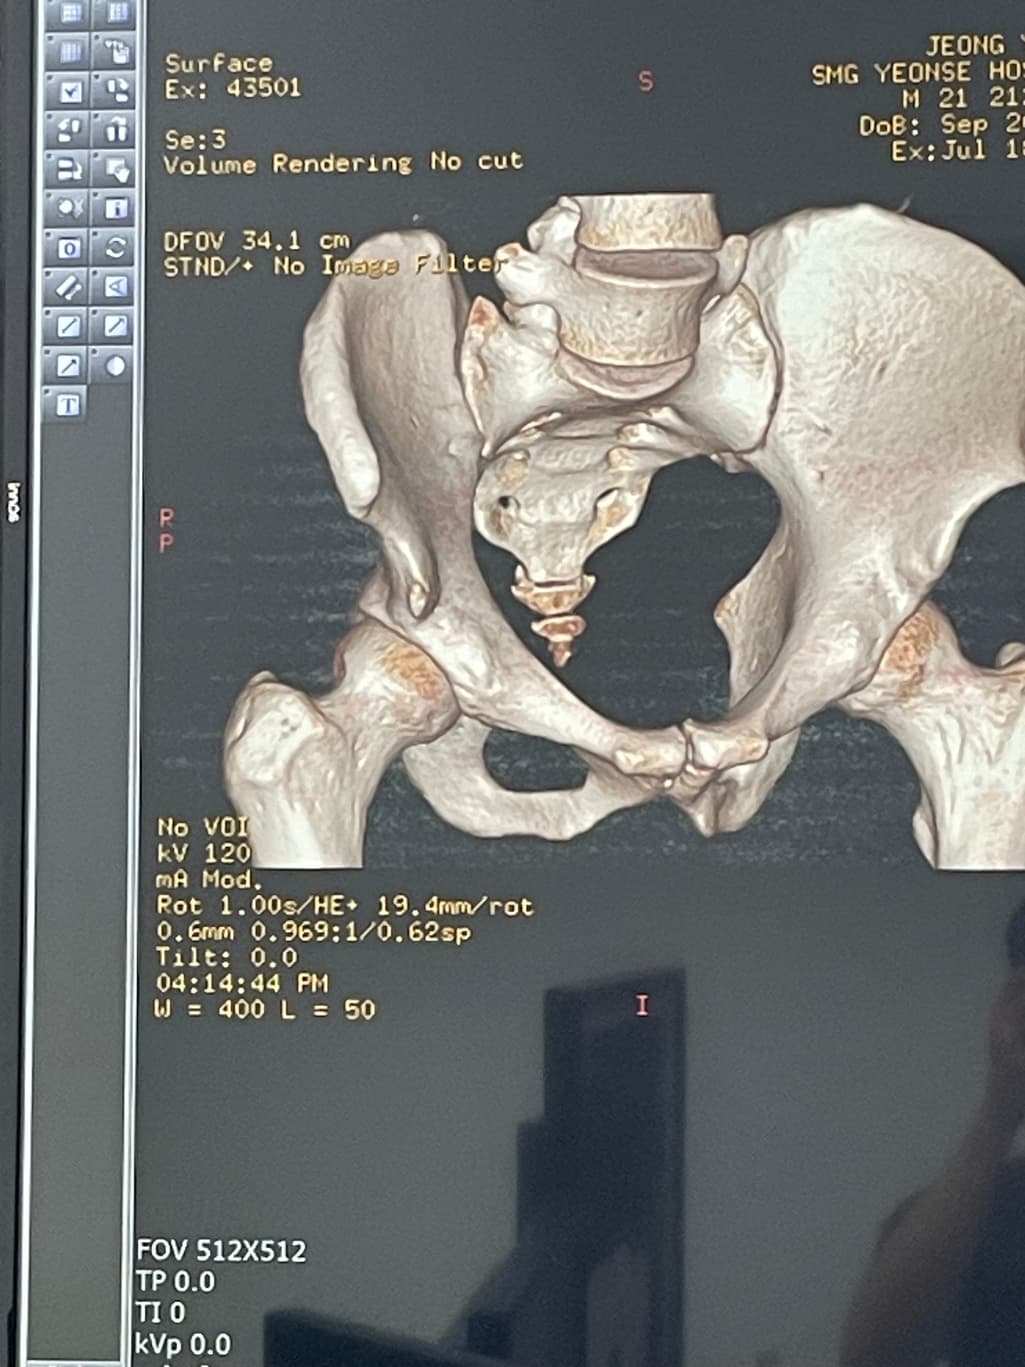

여기 골절 되었는데 재활이나 관리 방법 있을까요?

축구 슈팅 차다가 병원가니까 골절 이라는데 저 부분 명칭이랑 관리 방법 있을까요? 다행이 수술은 안해도 된다고 하던데.. 좋은 방법이 있나요..?

골절부분이 정확하게보이지않아서 확인하기어렵지만 골반뼈골절이라면 정도에따라서 수술이 필요할수도있으니 병원에서 전문의와 상담을받아보는것이 좋습니다

보통 골절의경우 충분한 고정과 물리치료그리고 골유합후에 재활치료가 필요할수있습니다 감사합니다~

골반뼈 골절의 경우 주로 치골이나 엉덩이 부위의 골절일 가능성이 있습니다 수술 없이 치료가 가능하다면 충분한 휴식과 고정이 필요하고 통증이 완화되면 물리치료를 통해 근육을 회복시키는 것이 중요합니다 골절 부위에 부담을 주지 않도록 조심하고 적절한 재활 운동으로 기능 회복을 돕는 것이 좋아요!